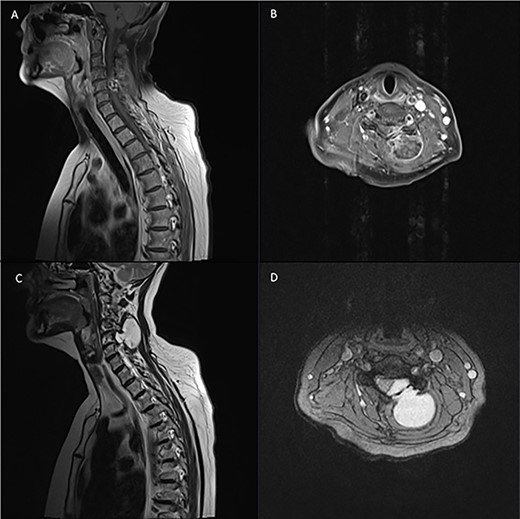

Pre-operative spinal imaging showed a well-circumscribed, cystic parasagittal spinal mass eroding through the lamina and pushing the thecal sac and largely indicative of a paraspinal myxoma (Fig. 1). The patient underwent a biopsy in the first instance to guide diagnosis and subsequently proceeded to resection of the tumour.

Pre-operative T1 and T2 weighted MRI: left-sided extra-axial mass at C4/5 hypointense on T1 and hyperintense on T2.

Pre-operative T1 post Gadolinium and T2 weighted MRI: left-sided extra-axial mass at C5/6 with heterogenous enhancement on T1 and hyperintense on T2. Moderate compression of the spinal cord and invasion into surrounding soft tissue.

Diagnostic spinal imaging showed a large mixed cystic solid destructive bony lesion arising from the bony elements at C5 with heterogenous enhancement (Fig. 3). A chest/abdomen/pelvic CT did not identify any further lesions.